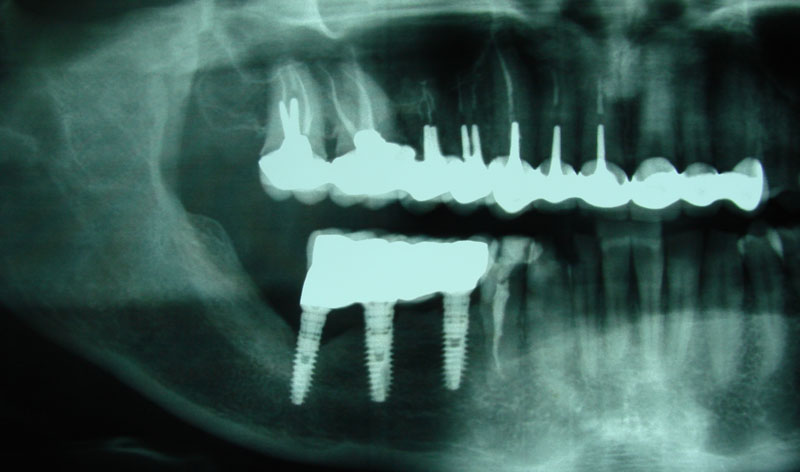

Son injertos del propio paciente extraídos del mentón o rama ascendente, destinados a aumentar la anchura del hueso indicados en maxilares con achura inferior a los dos milímetros.

Se deben fijar siempre con tornillos de 1.2 o 1.6 mm de osteosíntesis.

Terminada la reconstrucción ósea, es necesario esperar de 3 a 6 meses para la colocación de los implantes